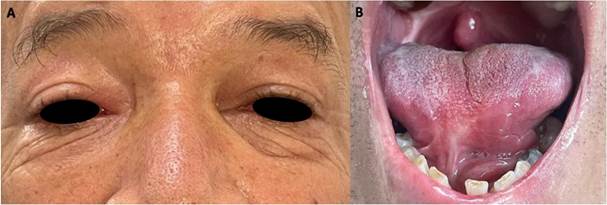

En el control de los 10 meses se evidencia resolución completa de las lesiones en OD y lengua (Fig. 4a y b), aunque se observa también las bridas cicatrízales que deja la paracoccidioidomicosis en mucosa. A pesar de que el manejo ha obtenido resultados satisfactorios, se debe continuar durante 6 meses más, para completar un año de medicación como lo prescribió infectología.